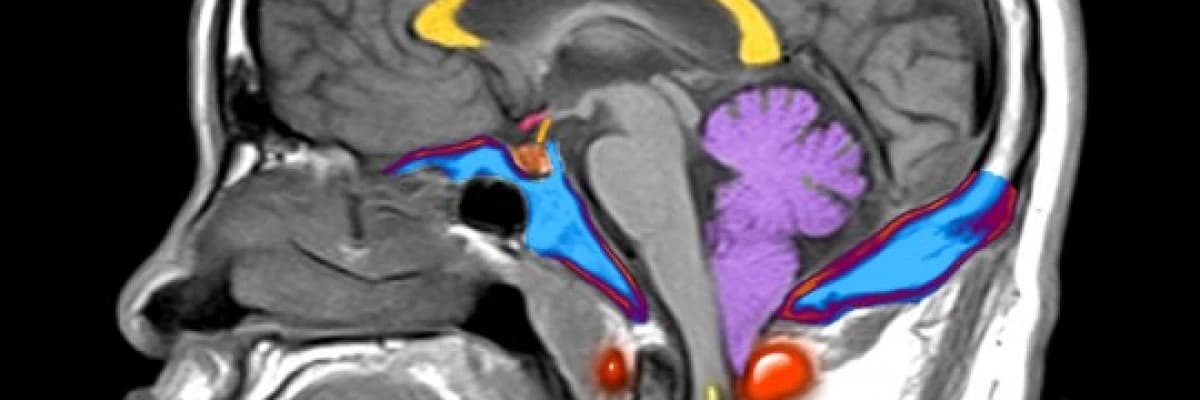

Manyetik Rezonans Görüntüleme (MRI): Tam anatomik görüntü elde etmek için önemlidir ve manyetik alan kullandığı için yan etkisi de yoktur. Beyin, beyincik, beyin sapı ve omurilik görüntülenerek Chiari I malformasyonunun tanısı ve eşlik eden ek anomalinin varlığı hakkında bilgi sahibi olunabilir.